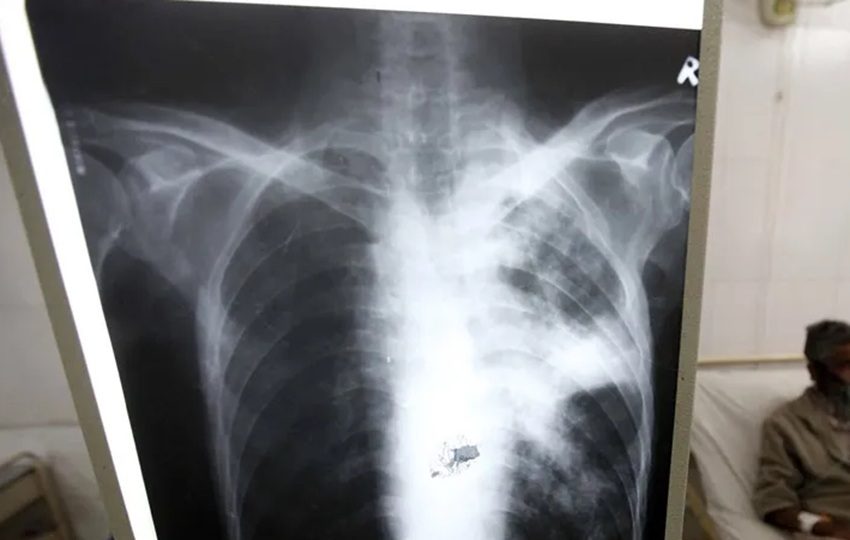

La tuberculosis puede ser mortal si no se trata. Foto: EFE

Un reciente estudio revela que la cepa Mycobacterium tuberculosis de linaje 2, predomina en la provincia de Colón, a diferencia del resto de Panamá, donde circula de manera principal la cepa de linaje 4.

En Colón, el 31.7% de los casos de tuberculosis corresponden a linaje 2, mientras que en América Latina este linaje es responsable del 10% de los casos.